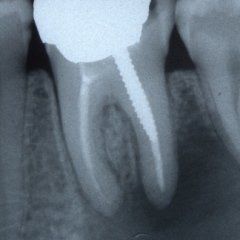

Il trattamento endodontico

P3: Il trattamento endodontico si rende necessario quando la polpa del dente, comunemente chiamata dai Pazienti “nervo” è stata irrimediabilmente danneggiata da carie penetranti, fratture dentali, traumi o da cause imputabili a pratiche odontoiatriche scorrette. A volte la devitalizzazione del dente si rende necessaria, in corso di riabilitazioni protesiche complesse, per prevenire possibili problemi di ipersensibilità o per poter coinvolgere nel progetto terapeutico di recupero denti già di per se compromessi dal punto di vista parodontale. Presupposto per ottenere il successo in tale terapia è l’applicazione di un serio protocollo operativo che prevede tra l’altro l’uso di un telo di lattice, chiamato comunemente “diga”, che consenta la detersione e la pulizia dei canali del dente in un ambiente sterile e il controllo delle diverse fasi del trattamento attraverso delle radiografie endorali.